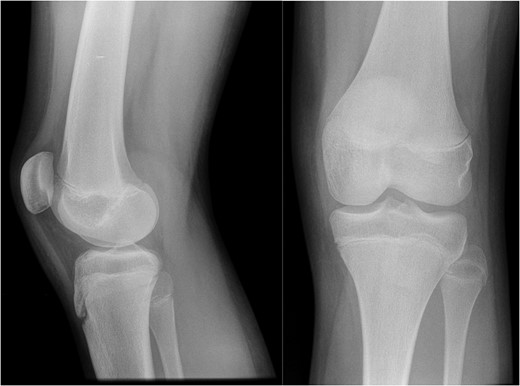

AP and lateral radiographs of the knee from the time of initial injury.

On examination at nine months she had medial tenderness and a positive McMurray's test, raising the suspicion of meniscal injury, for which the initial MRI investigation was performed. This scan showed a focal region of oedema centred in the medial aspect of the distal femoral physis with no other internal derangement, and she was managed with observation.